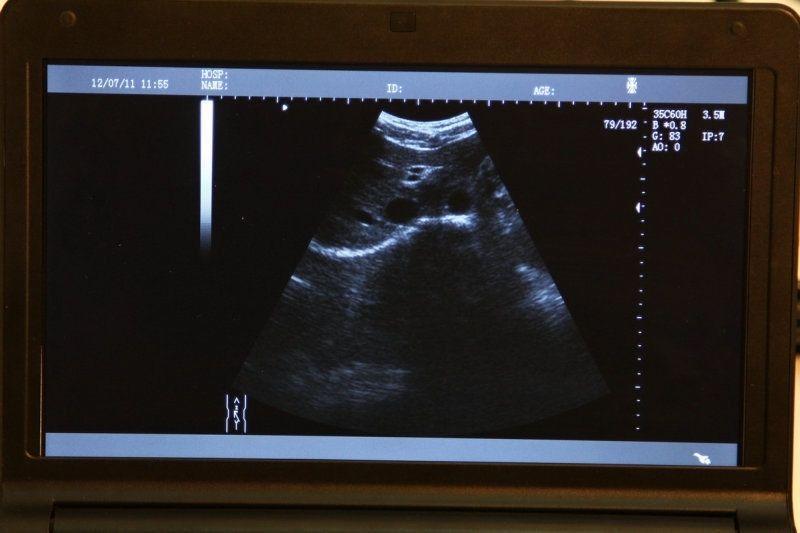

Advanced Technology for Accurate Imaging

The laptop ultrasound scanner

utilizes state-of-the-art technology to provide clear and accurate imaging, essential for diagnosing various medical conditions. With both transvaginal and convex probes, it caters to a wide range of examinations. This versatility ensures healthcare professionals can perform different types of scans with a single device, making it incredibly efficient. Moreover, the scanner’s lightweight design allows for easy transport, which is particularly beneficial in emergency medical situations.